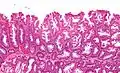

Micrograph of a sessile serrated lesion. H&E stain.

SSLs are diagnosed by their microscopic appearance; histomorphologically, they are characterized by (1) basal dilation of the crypts, (2) basal crypt serration, (3) crypts that run horizontal to the basement membrane (horizontal crypts), and (4) crypt branching. The most common of these features is basal dilation of the crypts.

Unlike conventional colonic adenomas (e.g. tubular adenoma, villous adenoma), they do not (typically) have nuclear changes (nuclear hyperchromatism, nuclear crowding, elliptical/cigar-shaped nuclei).